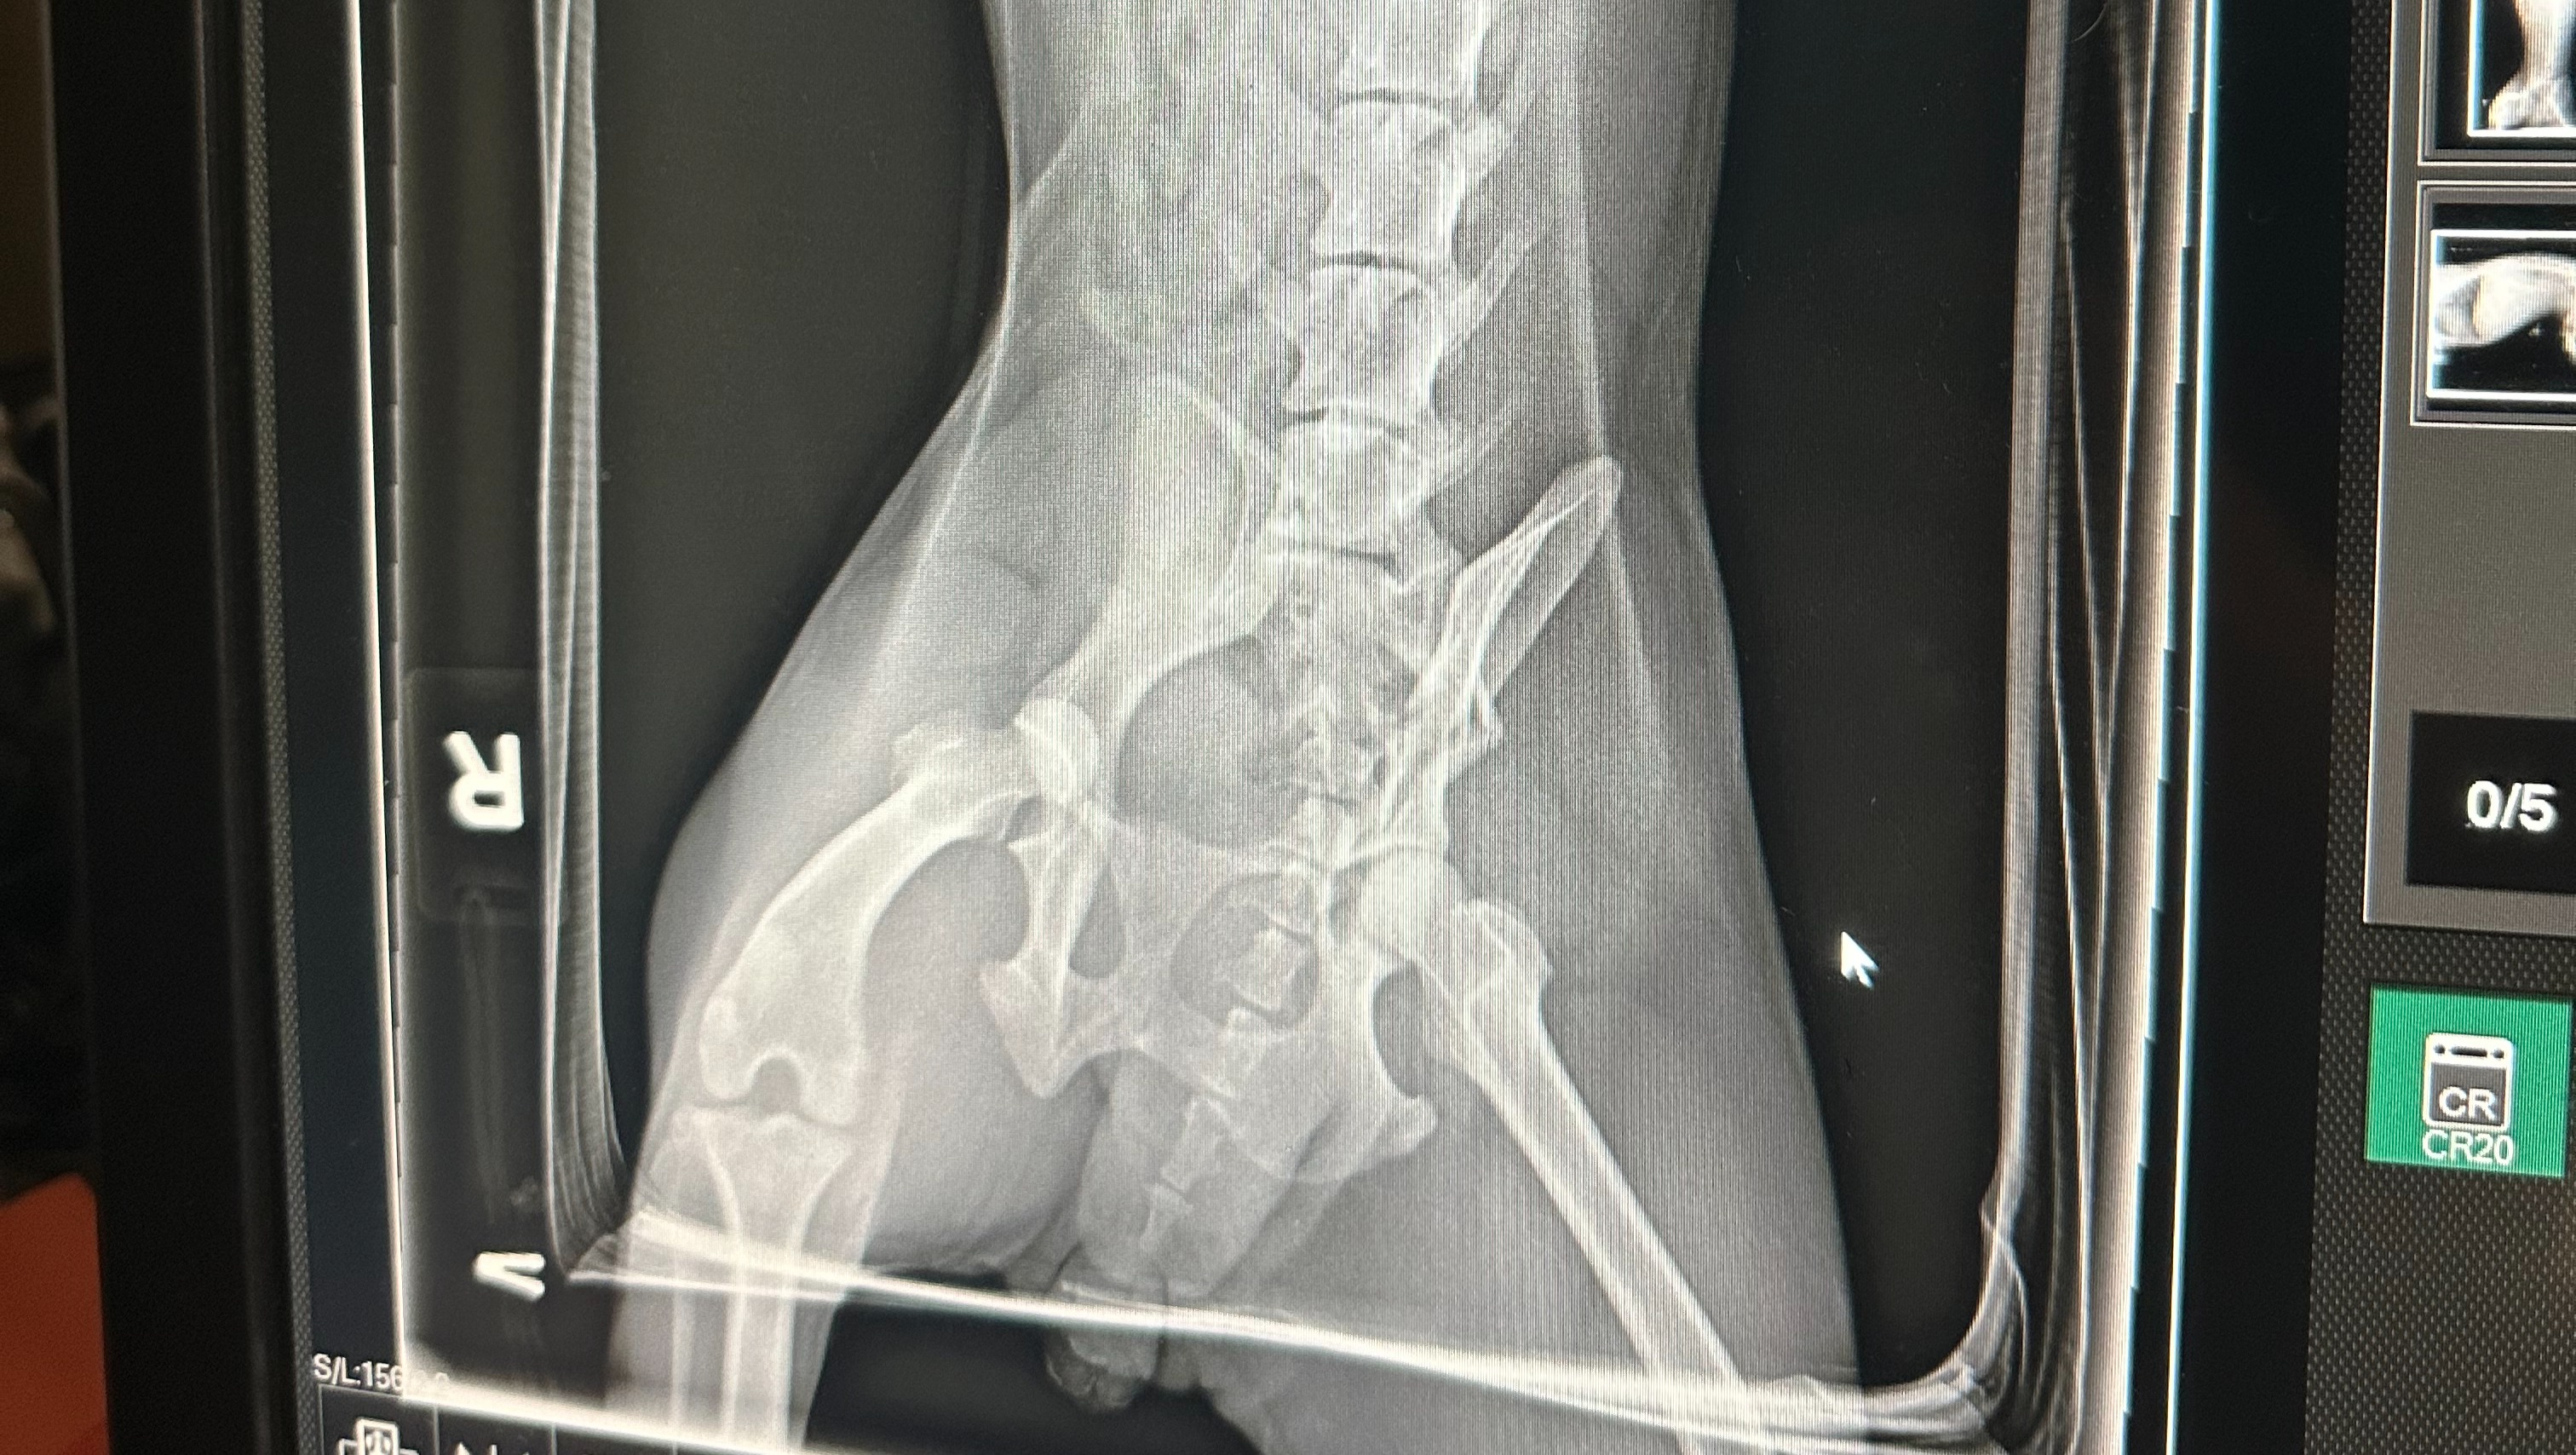

"Autumn" as we have decided to call her is in the current care of a vet and the initial cost to be seen was $510.23. The vet discovered that Autumn has a spinal fracture and a dislocated hip, that would require surgery to have the head of the femur removed. He states that this would heal quite well in a dog this size as she is a smaller dog. This surgery is estimated to cost between $1,136.60 - $1,407.17. She also needs IV fluids overnight as she is dehydrated, pain medication, and antibiotics for her wounds.